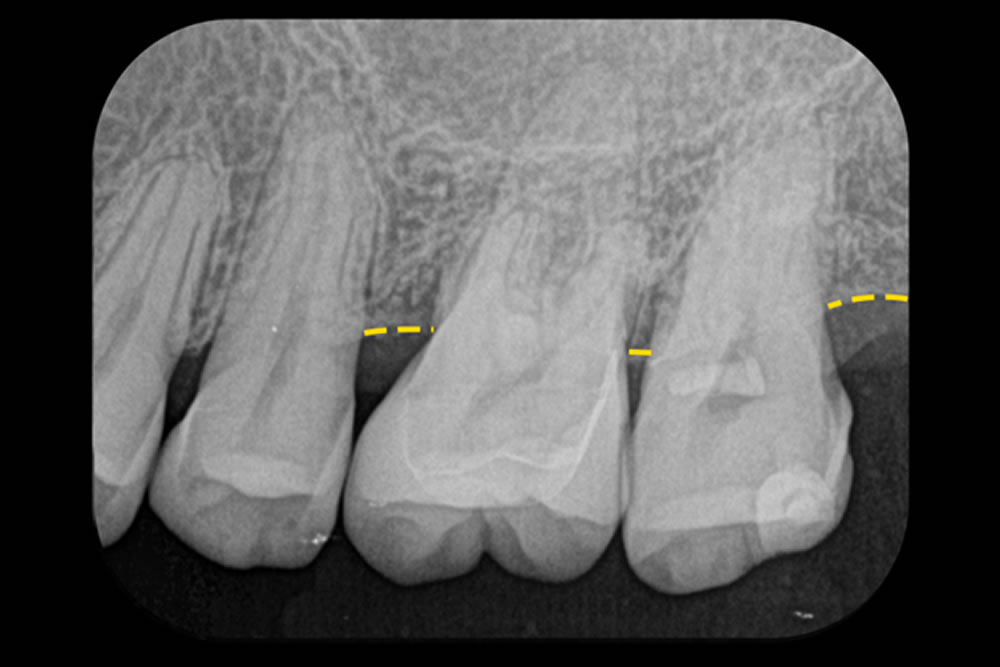

こちらの患者さまは、左上の奥歯2本(第一・第二大臼歯)に進行した歯周病があり、それぞれに「垂直性骨欠損」が見られ、分岐部にも炎症が及んでいました。非常に難易度の高い症例です。

当院では、体への負担を抑えるMIST(最小侵襲手術)を採用し、正確かつ丁寧な手術を行いました。第一大臼歯では、マイクロスコープ(顕微鏡)で分岐部を直視できるよう、口蓋側に縦方向の切開を加えて視野を確保しました。

感染組織の除去にはEr:YAGレーザー(エルビウムレーザー)を使用し、同時に骨再生を促す処理(デコルチケーション)も実施。第二大臼歯では、骨の欠損部を避けるよう切開位置を工夫し、治癒や歯ぐきの安定に配慮しました。治療から2年半が経過した現在も、歯と歯ぐきは良好な状態を維持しています。